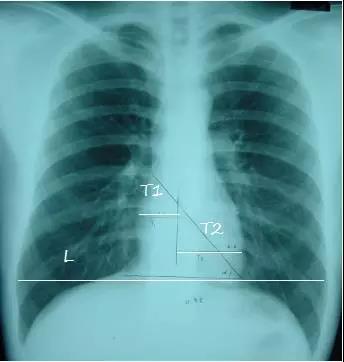

T1:心脏最右缘至前正中线距离

T2: 心脏最左缘至前正中线距离

L:通过膈肌顶部至两侧胸廓内沿并平行于膈肌的线

心胸比=(T1 T2)/L

1.正常<=0.50

2. 轻度增大 0.51-0.55

3. 中度增大0.56-0.60

4. 重度增大>=0.60